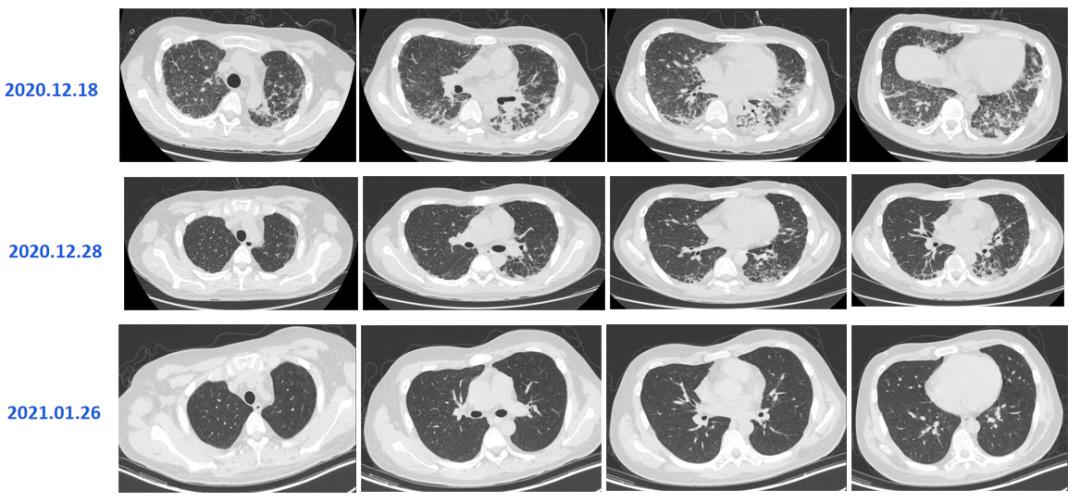

2023-03-30胸部CT

临床病例(二):林某某,男,73岁,2023年3月30日因「反复咳嗽、咳痰1月余,加重1周。」入院。1周前无明显诱因出现咳嗽、咳痰、气喘加重,伴腹痛,进食后明显,近1周消瘦明显。

既往史及个人史:2023年1月27日因「泡沫尿半年、双下肢水肿8天」于福州某三甲医院住院治疗,2023年1月30日行「肾穿刺活检」,术后病理:膜性肾病;后「甲泼尼龙、他克莫司」。

查体:体温:36.5℃;脉搏:58次/分;呼吸:18次/分;血压:154/85mmHg,双肺呼吸音粗,可闻及干湿性啰音。

血气分析:pH:7.45,pCO2:27mmHg,pO2:82mmHg,HCO3-:19mmol/L,SaO2:96.7%,氧合指数:282。

血常规:粒细胞百分比92.8%↑、淋巴细胞百分比3.8%↓、淋巴细胞计数0.24*10^9/L↓、单核细胞百分比1.8%↓、嗜酸性细胞百分比0.3%↓。

CRP:105.0mg/L↑ PCT:1.08ng/ml↑ 血沉:97.0mm/h↑ 急诊N端B型钠尿肽前体:3035.0pg/mL。

生化:尿素19.9mmol/L↑、肌酐118.4μmol/L↑、葡萄糖40.07mmol/L、总蛋白51.5g/L↓、白蛋白21.7g/L↓、肌酸磷酸激酶257.6U/L↑、肌酸激酶同工酶41.3U/L↑、乳酸脱氢酶297.1U/L↑、钾5.51mmol/L↑、钠130.1mmol/L↓、氯89.9mmol/L↓、二氧化碳22.1mmol/L↓、渗透压331.2mmol/L↑。

诊治经过如下:

患者既往有肾脏基础疾病,使用激素及免疫*制剂抑**2个月,此次肺炎病情进展迅速,胸部CT影像学表现病灶多样,需立即完善纤维支气管镜肺泡灌洗明确病原菌。

该患者为诺卡菌、耶氏肺孢子菌、巨细胞病毒、曲霉菌、非结核分枝杆菌、酵母菌的复杂感染,考虑患者多种药物联合治疗肝肾负担重,暂先给予SMZ注射液、更昔洛韦、伏立康唑及美罗培南治疗,病情得到明显缓解,后调整伏立康唑为艾沙康唑,停用更昔洛韦后加用抗利福平、乙胺丁醇、克拉霉素进行抗非结核分枝杆菌治疗。

复查患者炎症指标明显好转,胸部CT复查较前明显吸收。

对于复杂感染患者,多种抗菌药物联合使用会导致肝肾功能损害,需权衡利弊,需要优先处理易导致疾病快速进展的病原菌如PJP、巨细胞病毒、细菌,后处理增殖缓慢的病原菌,如曲霉菌、结核、非结核分枝杆菌等。

2022-7-13胸部CT

临床病例(三):甘某某,男,50岁,2022年7月12日因「发热,、咳嗽、咳痰、气喘10余天,加重2天」入院。痰色白不易咳出,体温最高38.5℃。外院予「莫西沙星+头孢他啶」抗感染,「甲强龙40mg」抗炎,仍反复发热,2天前咳嗽、咳痰、气喘加重。

既往史及个人史:2022年2月于广西省人民医院行「肾移植术」,后规律服用「吗替麦考酚酯胶囊、他克莫司」抗排斥。

查体:T 37.3℃,P 118次/分,R 25次/分,BP 118/89mmhg。双肺呼吸音粗,未闻及干湿性啰音和胸膜摩擦音。心腹查体未见明显异常。

血气分析:PCO2:26.9mmHg↓、PO2:56.2mmHg↓、实际碳酸氢根17.2mmol/L↓、标准碳酸氢根19.8mmol/L↓、总CO2:40.5mmol/L↑、实际剩余碱-5.4mmol/L↓、标准剩余碱-6.4mmol/L↓、氧饱和度88.9%↓、氧合血红蛋白86.6%↓、还原血红蛋白10.8%↑、P50:26.55↓。

血常规:白细胞 8.22X10^9、粒细胞百分比 85.1%↑、粒细胞计数 7.65X10^9↑、淋巴细胞百分比 7.4%↓、淋巴细胞计数 0.45X10^9↓、嗜酸性细胞百分比 0%。

CRP:106mg/L↑

患者既往有肾移植病史,使用激素及免疫*制剂抑**,此次肺炎病情进展迅速,胸部CT影像学符合PJP或巨细胞病毒改变,需立即给予PJP及更昔洛韦诊断性治疗,并积极完善纤维支气管镜肺泡灌洗明确病原菌。

2022年7月14日的BALF-mNGS结果,检出耶氏肺孢子菌。

患者的呼吸道病原体谱抗体,EB病毒、巨细胞病毒DNA,肺炎支原体,T-SPOT,术前四项均未见异常。

2022年7月17日:患者气喘较前明显好转,改口服SMZ;7月18日:复查胸部CT。患者仍有活动性气喘,暂续前治疗;7月20日:气喘明显加重,急查血气;7月22日:炎症指标上升,转ICU行气管插管+呼吸机辅助呼吸,CRRT。

2022年7月18日,患者胸部CT见双肺间质性炎症范围较前扩大,考虑PJP感染导致的间质性炎症持续渗出。

患者属重症PJP,给予静脉使用SMZ注射液病情一度好转,但因经济原因,改为口服SMZ治疗,后病情进展迅速。

2022年7月24日,BALF-mNGS检出耶氏肺孢子菌、肺炎克雷伯菌。肺炎克雷伯菌系院内感染。7月28日,多次复查血常规提示血小板进行性下降;8月8日:抗生素降阶梯;8月10日:气管插管2周,暂难脱机,需行气管切开,血小板低,输注血小板,择期行气切;8月13日:血小板进行性下降,感染消耗可能。血小板27X109/L、CRP89.2mg/L;8月16日:复查血常规示三系进行性下降,降钙素原升高15.6ng/ml,感染加重;8月17日:炎症指标较前明显升高,调整抗生素。血小板16X109/L、CRP272mg/L;8月18日:患者深昏迷,FIO2100%,血氧饱和度波动于60%-80%,去甲肾上腺维持血压,随时可能出现死亡风险,患者家属强烈要求出院,劝阻无效,予办理自动出院。血小板11X109/L、CRP326mg/L。

从该例病例,我们可以看到,PJP的早期诊断和治疗非常关键,及时早期使用SMZ的治疗对预后起着决定性的作用,对于重症PJP,建议尽早使用SMZ注射液,并序贯口服治疗。